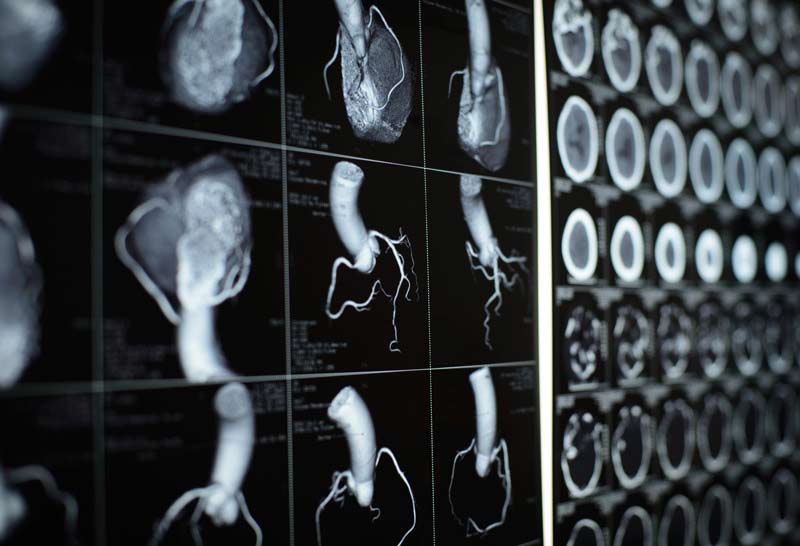

Коронарография — это высокоточный метод лучевой диагностики, который позволяет получить детализированные послойные изображения сердца и коронарных сосудов. Обследование проводят с контрастированием или без него в зависимости от цели исследования. Во время сканирования анализируют просвет и проходимость коронарных артерий, а также состояние сердечных структур.

КТ сердца с контрастом показывает просвет коронарных артерий, а также анатомию и -сердечных и -структур. Патологии, которые покажет КТ сердца, могут включать:

КТ сердца позволяет получить трехмерную модель органа и его сосудов с высоким разрешением. Метод позволяет выявлять мельчайшие изменения, а также подробно описывать патологические процессы, зафиксированные или заподозренные во время УЗИ или ЭКГ. Структуры, входящие в КТ-диагностику сердца:

Мультиспиральная КТ сердца охватывает всю зону обследования за одно задержку дыхания, минимизируя радиационную нагрузку на организм пациента. Рентгенолог может изменять угол обзора, толщину срезов и плоскость сканирования, что облегчает оценку сердечно-сосудистой анатомии и снижает риск диагностических ошибок.